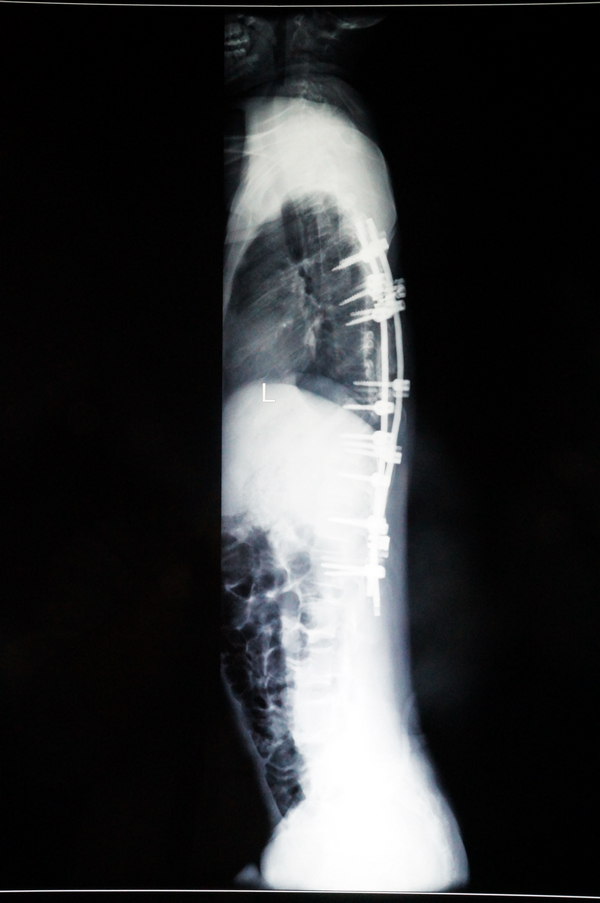

现在,经过手术后的小松脊柱外观基本恢复了正常,他感到背部没有明显的疼痛,且背部的手术伤口也愈合良好,没有发热头晕头痛和恶心呕吐等不适症状,饮食睡眠都很好,四肢感觉、运动、肌力正常。

小松术后的X光片2